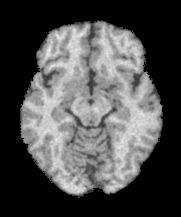

Magnetic Resonance Imaging (MRI) is a critical and widely used medical modality due to its noninvasive nature and ability to produce high-quality images of human organs and tissues. Segmentation in MRI refers to the process of dividing the acquired image data into specific tissues or regions of interest (ROIs). In the context of brain slice MRI data, this often involves distinguishing between cerebrospinal fluid (CSF), gray matter (GM), and white matter (WM), in 2D image slices as depicted in Fig. 1. Research topics on brain anatomy and functionality (e.g., Alzheimer’s disease, tumor detection, neurodegenerative processes, etc.) demand reliable segmentation tools since their outcomes directly impact the subsequent analysis of the brain slice MRI. Therefore, the development of any accurate MRI segmentation framework has to deal with the following issues:

(1) where can be interpreted as a smoother version of . With a little abuse of notation, we indicate the equation (1) as a cartoon-texture (CT) decomposition (even though we do not aim to compute a proper CT decomposition), where is the ‘cartoon’ depicting the structural component, and the ‘texture’ part including oscillatory components, like texture and noise, as shown in Figure 1.

Figure 3 illustrates the workflow of the algorithm SegMIC2T using the slice060 with low (top row) and moderate (bottom row) levels of the combined artifacts. The noise estimation step splits the original MRI slice into a cartoon image (second column) and a texture image (third column) (1). The correction step, coinciding with the application of the proposed multiaffine ADMM method, produces a denoised and debiased version of the original slice, whose th pixel corresponds to (fourth column). In the last step, the segmentation of the original slice is produced by clustering the pixels in the corrected image (fifth column).